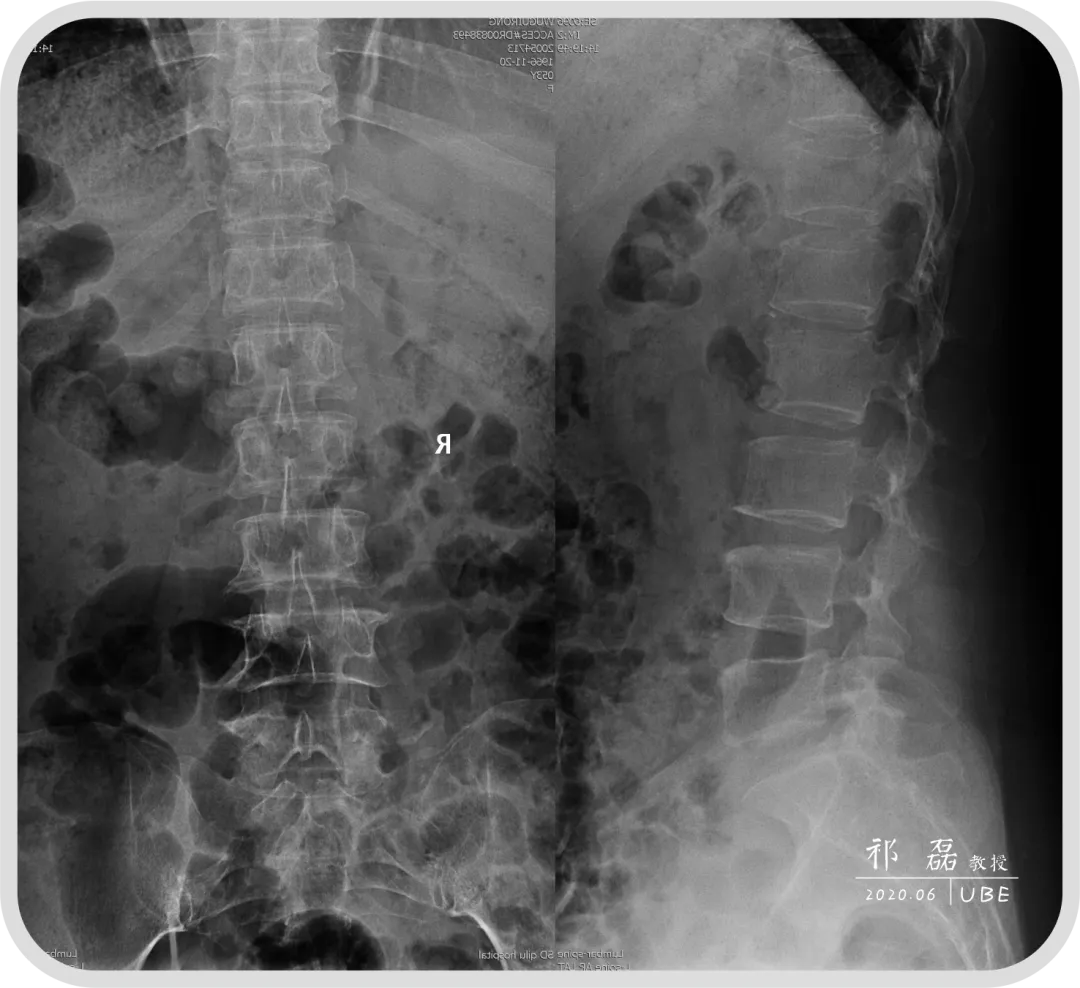

患者:吴某,女,53岁,腰痛及双下肢疼痛麻木5年余,加重1月余,间歇性跛行约200米。于近日入我院查体,下腰椎棘突及椎旁肌深压痛,双下肢感觉运动正常。双侧直腿抬高试验(-),双侧踝反射(-),入院诊断为:腰椎管狭窄症。

图1:腰椎正侧位+过伸过屈位X线